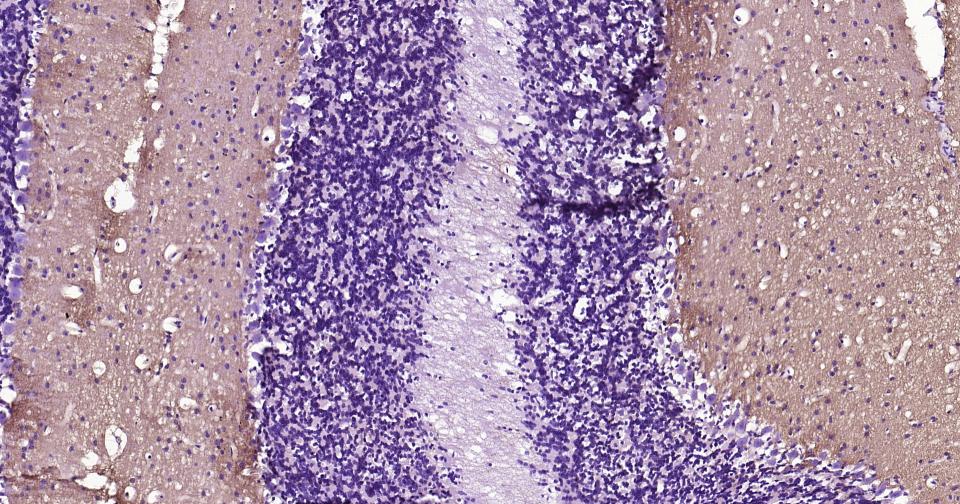

Paraformaldehyde-fixed, paraffin embedded Human Cerebellum; Antigen retrieval by boiling in sodium citrate buffer (pH6.0) for 15 min; Antibody incubation with GAP43 Monoclonal Antibody, Unconjugated(bsm-52565R) at 1:200 overnight at 4°C, followed by conjugation to the bs-0295G-HRP and DAB (C-0010) staining.

Paraformaldehyde-fixed, paraffin embedded Rat Cerebellum; Antigen retrieval by boiling in sodium citrate buffer (pH6.0) for 15 min; Antibody incubation with GAP43 Monoclonal Antibody, Unconjugated(bsm-52565R) at 1:200 overnight at 4°C, followed by conjugation to the bs-0295G-HRP and DAB (C-0010) staining.

Paraformaldehyde-fixed, paraffin embedded Mouse Cerebellum; Antigen retrieval by boiling in sodium citrate buffer (pH6.0) for 15 min; Antibody incubation with GAP43 Monoclonal Antibody, Unconjugated(bsm-52565R) at 1:200 overnight at 4°C, followed by conjugation to the bs-0295G-HRP and DAB (C-0010) staining.